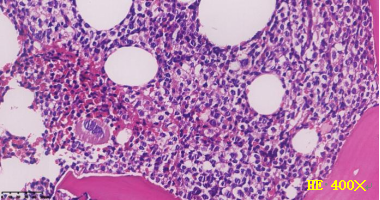

骨髓活检结果回报:符合T-ALL,且免疫组化提示约5-8%肿瘤原始细胞同时表达CD117及MPO,HE、CD3、CD117、MPO组化图如下: